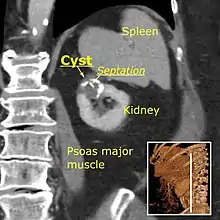

The complex cyst can be further evaluated with doppler ultrasonography, and for Bosniak classification and follow-up of complex cysts, either contrast-enhanced ultrasound (CEUS) or contrast CT is used.[8]

Renal ultrasonography of a simple renal cyst with posterior enhancement.